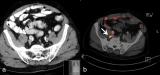

本例患者主要症状为左足局部慢性疼痛。常规影像学检查可见多发侵袭性的溶骨病灶,骨显像和18F-FDG PET显像均显示病灶呈高摄取,且局限于左下肢远端,最终经手术活检证实为上皮样血管内皮瘤,并进行局部肢体热灌注化学治疗。 2022-06-19 核医学PET/CT